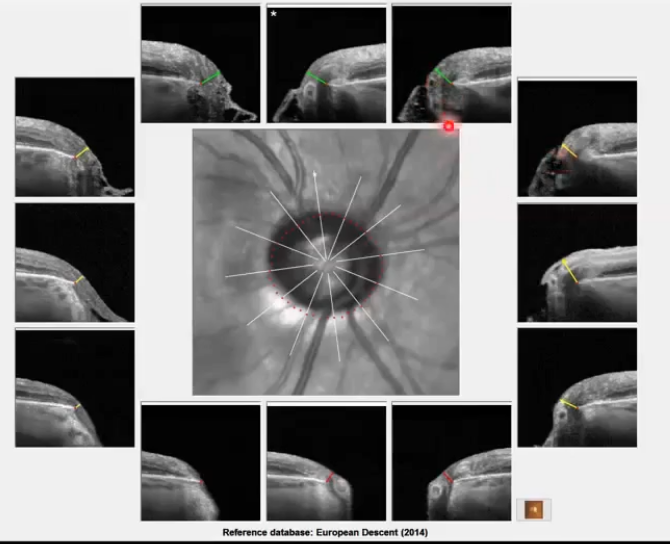

oct scans of the onh (2): BMO scans

6 radial B scans through the onh

b scan along each of the white lines

identify bruchs membrane opening as edge of onh

used for identifying minimum rim width around disc

BMO scans for assessing nrr

bright line with red dot at end of it whih is the end of bruchs membrane

so everything inside that is part of the onh

has ideniftied minimum distance between red dot ( bruch membrane ending) and top of the nerve fibre layer

sometimes the subjective disc margin ( green dots) does not correspond to the actual opening in bruchs membrane (red dots); not in the same place as the red dots. mismatch

so what does the mismatch mean then for analysis?

can therefore sometimes identify areas of thinner rim than subjectively assessed

useful in glaucoma